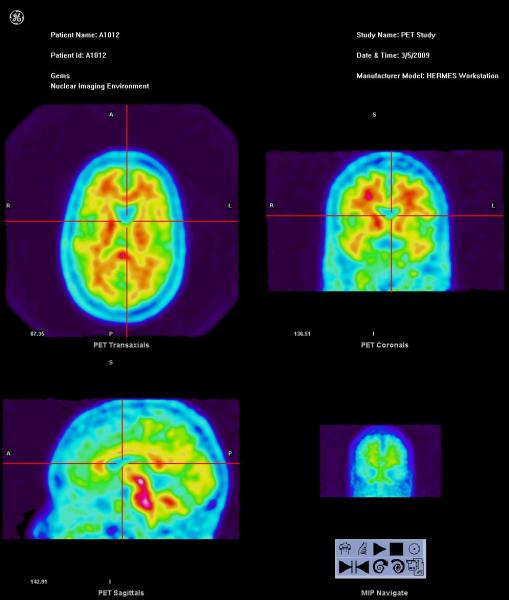

Vizamyl (flutemetamol F-18) scan of a normal brain.

Vizamyl, flutemetamol, FDA, GE